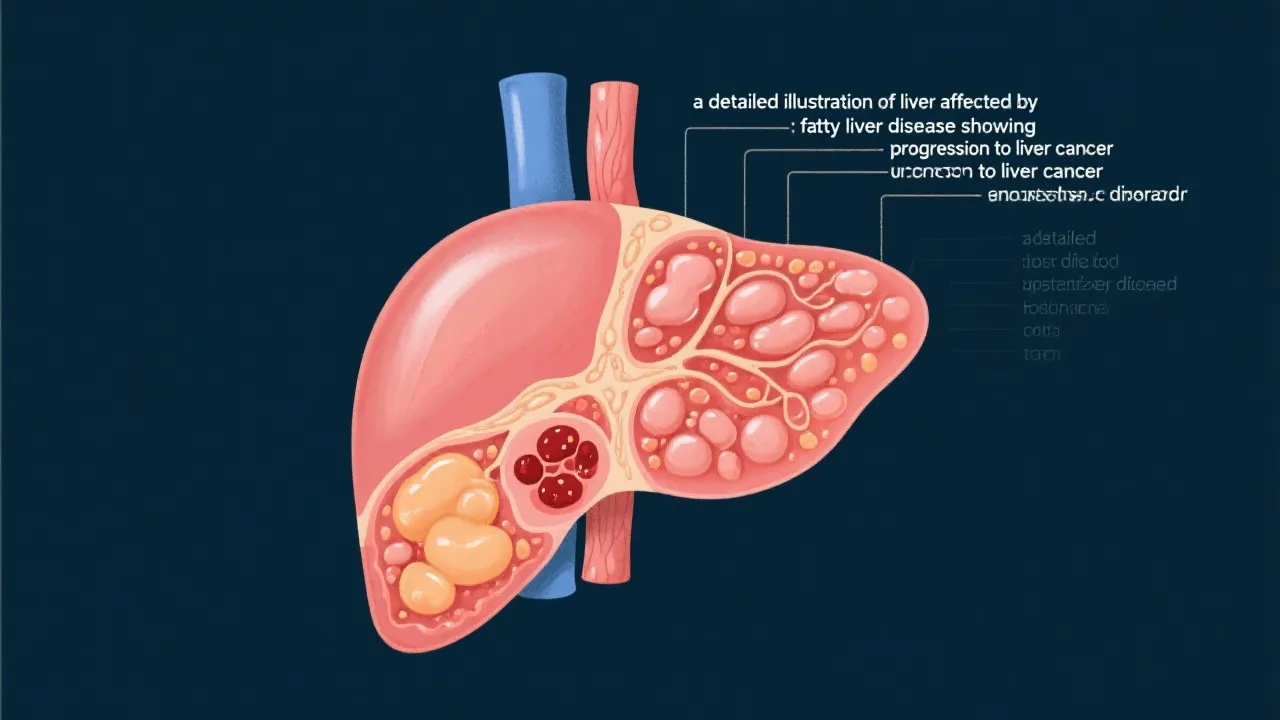

Nonalcoholic fatty liver disease (NAFLD) is increasingly recognized as a significant health concern worldwide due to its potential progression to hepatocellular carcinoma (HCC), commonly known as liver cancer. Hepatologists reveal that while NAFLD is primarily marked by excessive fat accumulation in the liver, its very severe complication is the development of HCC. Understanding this link is crucial for developing effective strategies to manage and treat the condition. Moreover, the global prevalence of obesity and type 2 diabetes, which are significant risk factors for NAFLD, underscores the urgency of addressing this public health challenge.

NAFLD-related HCC has become a topic of interest among researchers and healthcare professionals. The liver's vulnerability to fat accumulation can lead to inflammation, fibrosis, cirrhosis, and eventually cancer. While traditional risk factors for liver cancer include chronic hepatitis infection and alcohol abuse, NAFLD is now recognized as a major risk angle, especially in Western countries. This shift is not merely an epidemiological observation; it is also reflected in changing patterns of liver cancer incidences, which show a marked increase associated with rising rates of obesity and sedentary lifestyles. Researchers are working diligently to elucidate the biological and molecular mechanisms linking these two conditions.

The exact mechanism by which NAFLD progresses to HCC is complex and multifaceted. Genetic predisposition, lifestyle choices, and other metabolic comorbidities such as obesity and type 2 diabetes contribute significantly to this progression. A key element in this relationship is the development of nonalcoholic steatohepatitis (NASH), a more severe form of NAFLD characterized by inflammation and liver cell damage. Current studies suggest that molecular changes in liver tissue, induced by lipid metabolic disturbances, play a key role in carcinogenesis.

In particular, the accumulation of toxic lipids and inflammatory cytokines can provoke oxidative stress, leading to DNA damage and genomic instability, which are critical factors in the development of cancer. Moreover, insulin resistance, often associated with obesity and metabolic syndrome, plays a significant role in this pathway, augmenting hepatic fibrosis and the likelihood of malignancy. Other factors, such as aging and certain genetic mutations (like those affecting the PNPLA3 gene), can further exacerbate the risk of HCC among individuals with NAFLD.

Over time, NAFLD can cause inflammation and damage to liver tissues, leading to cirrhosis and increasing the risk of liver cancer. The progression typically involves the transition from NAFLD to NASH, which heightens the risk of liver cell malignancy.